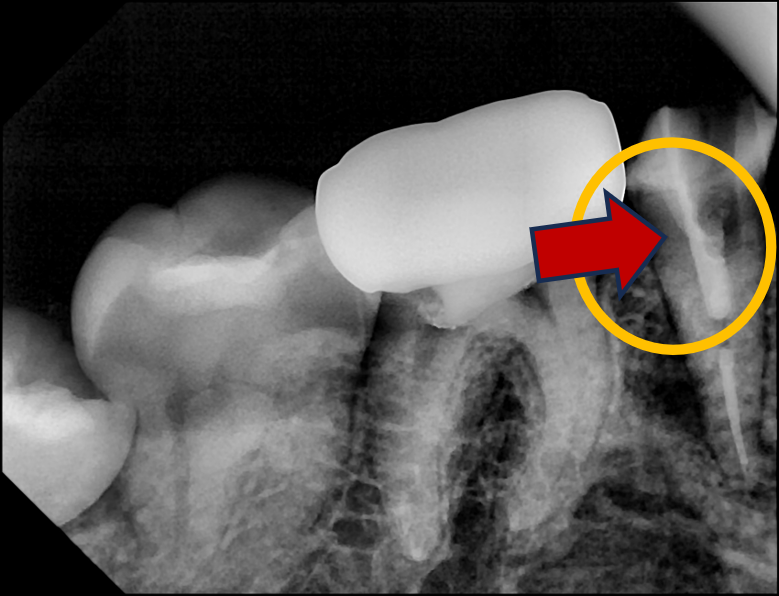

이쯤에서 작은 엑스레이를 한 번 찍는다.

재신경치료를 위해 파이버 포스트를 제거하는 과정에서 엑스레이를 찍어서 상황을 파악

다행히 축의 방향은 맞는데, 지금부터는 조금 왼쪽으로 접근을 해야한다.

재신경치료를 위해 파이버 포스트 제거가 어느 정도 됐는지 엑스레이로 확인

왼쪽으로는 그만! 이제부터는 다시 오른쪽으로 방향 수정해서 아래로 접근.

재신경치료를 위해 파이버 포스트를 제거하고 근단부의 끝까지 접근한 엑스레이 사진

흐아~~ 다행히 포스트를 제거하고 뿌리끝에 접근하는 데에 성공했다!!

아무튼 중간에 4장의 엑스레이를 찍어가며, 무사히 포스트 제거에 성공.